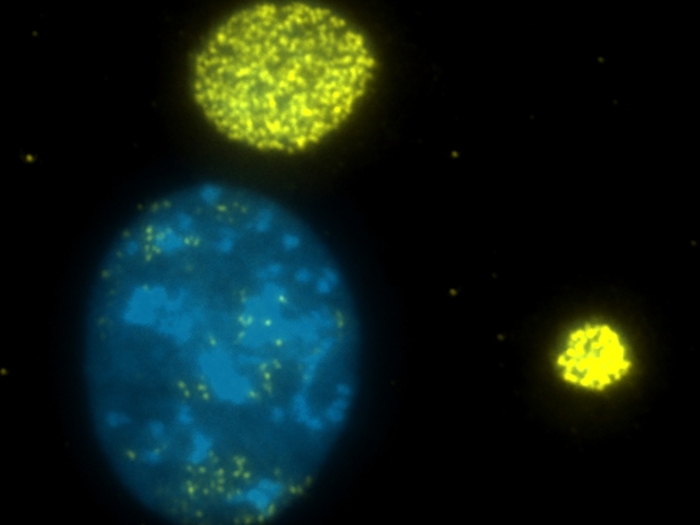

High levels of ammonia in colon tumors inhibits T cell growth and response to immunotherapy

In mouse models and serum samples, an FDA-approved drug that lowers ammonia levels made the tumors more sensitive to treatment.